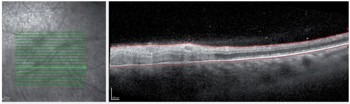

Diagnosis of ARN is clinical, supported by laboratory investigations, but multimodal imaging can aid diagnosis. Ultra-widefield photography can be useful to identify peripheral retinitis in ARN, particularly when the fundal view is obscured by vitritis or the patient is photophobic and difficult to examine. OCT imaging is not always possible through the retinitis as it is frequently too peripheral; when possible, we see hyperreflectivity and thickening of the inner plexiform layer early in presentation, followed by full thickness involvement of all retinal layers (Fig 4)5.

Fig 4. OCT imaging of patient in Fig 3, through retina (inferotemporal posterior pole) demonstrating full thickness hyperreflectivity and loss of retinal architecture ie. full thickness retinitis